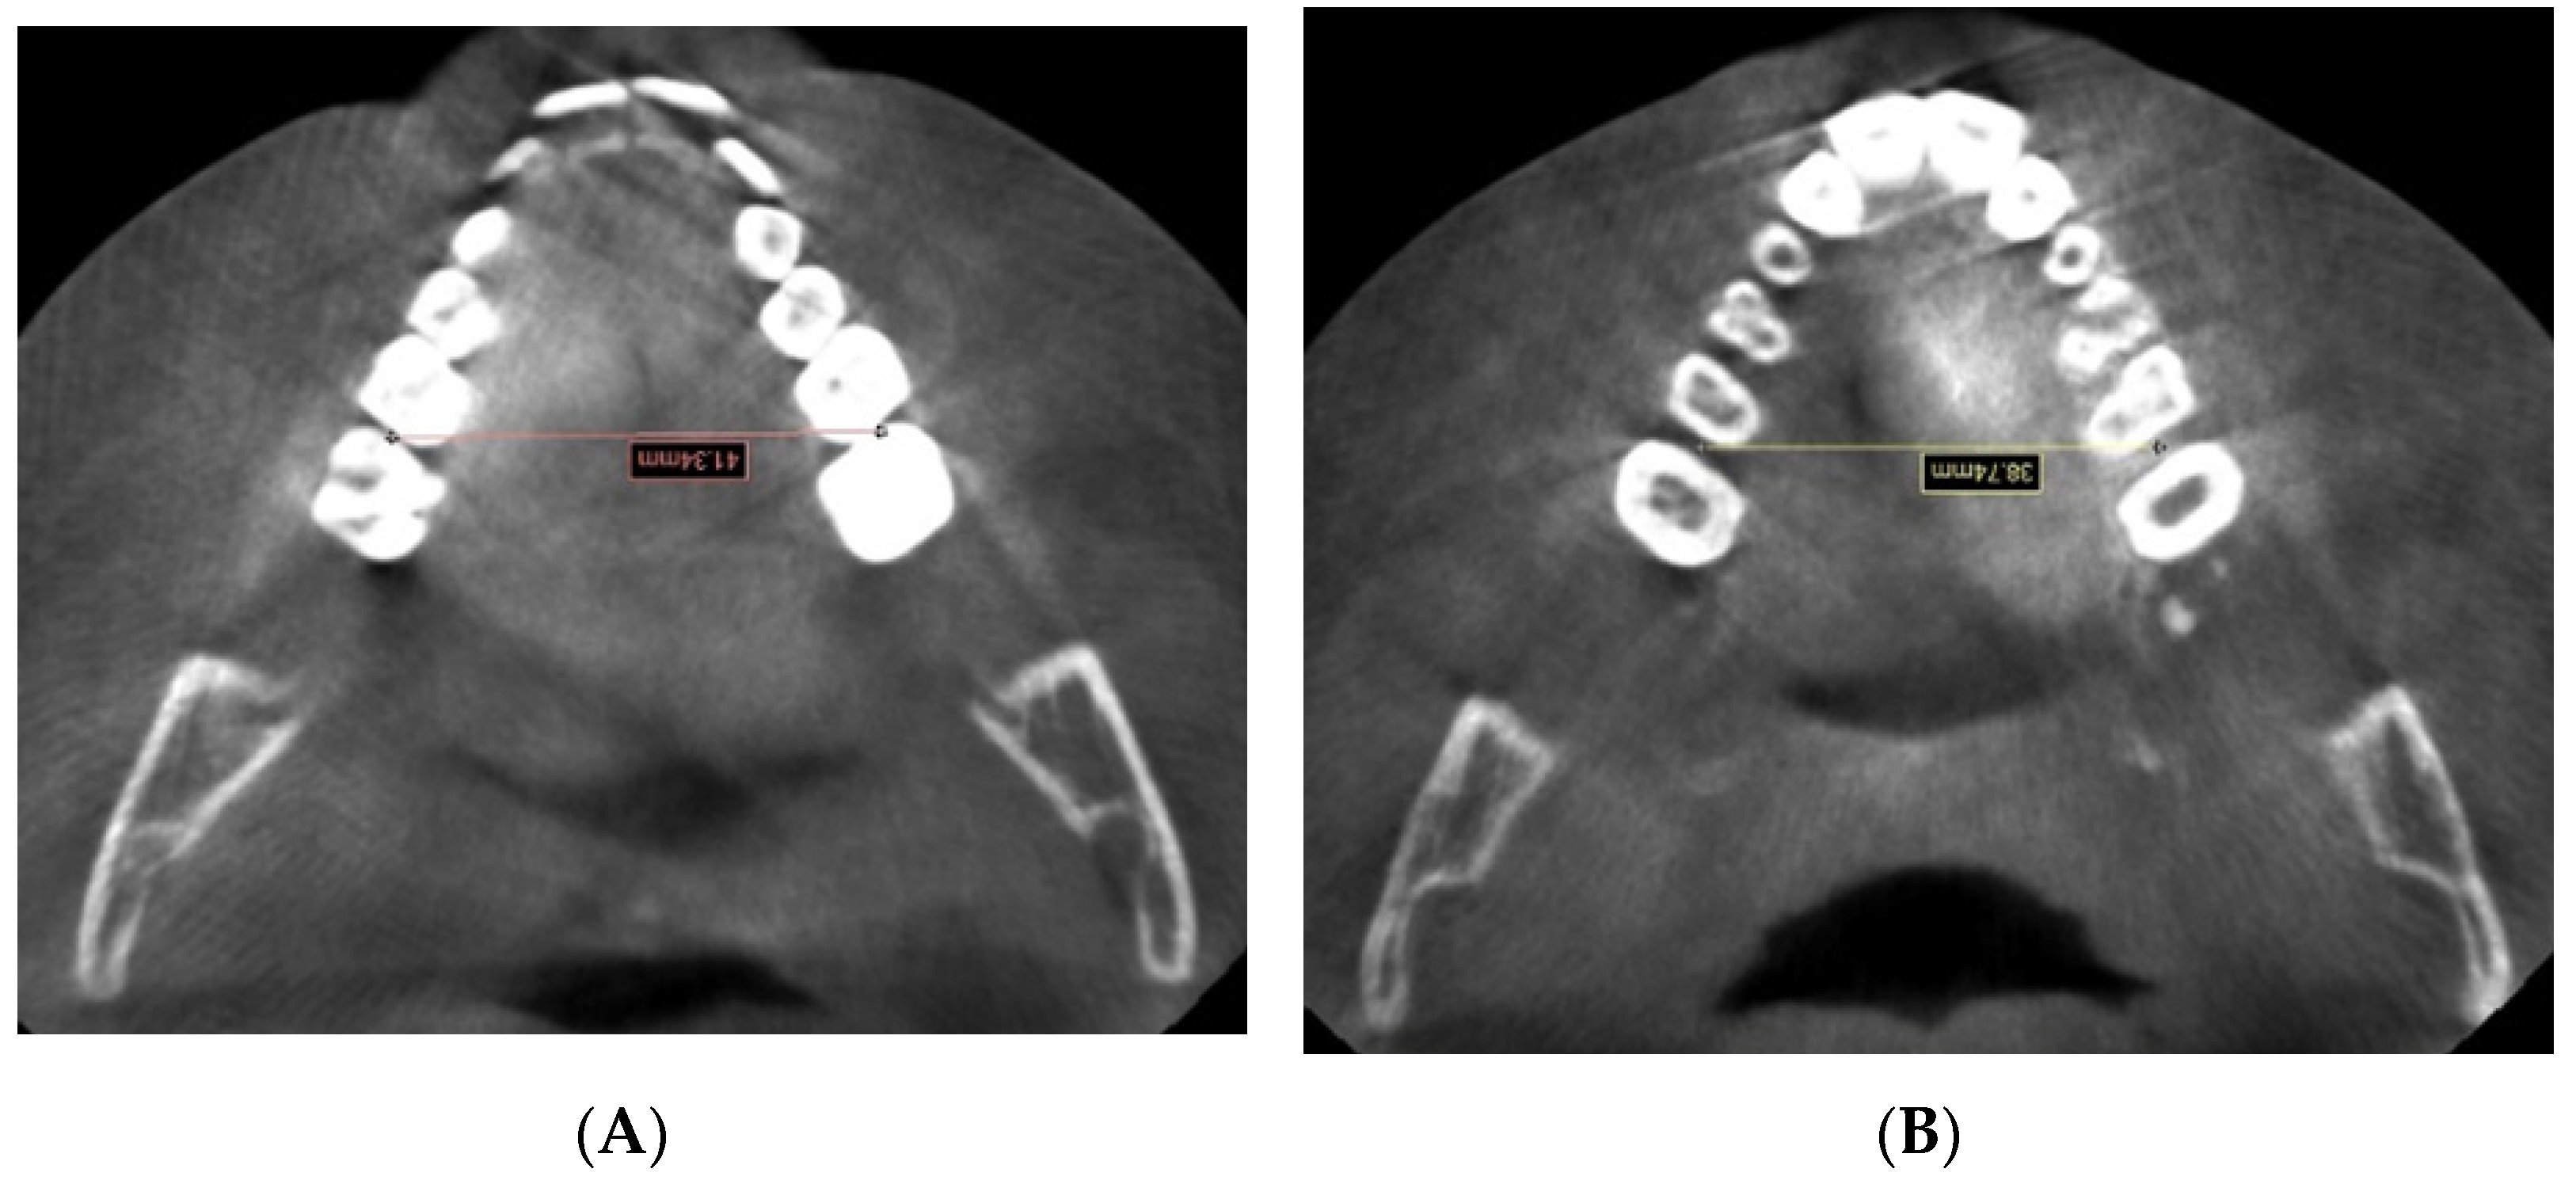

2. Materials and Methods

| 6RIM-6LIM | Distance between the interproximal contact point on the | |

| mesial surface of the first right molar and the interproximal | ||

| contact point on the mesial surface of the first left molar | ||

| 6RABM-6LABM | Distance between the mesial surface of the first right molar | |

| and the mesial surface of the first left molar at the | ||

| alveolar bone level | ||

| 6RABM-6LABM | 36.18 (2.88) a | 40.85 (2.59) b | p < 0.0001 | 36.47 (2.77) a | 41.25 (2.74) b | p < 0.0001 | NS |

| 6RIM-6LIM | 37.40 (2.79) a | 41.71 (2.85) b | p < 0.0001 | 39.49 (6.58) a | 43.97 (6.71) b | p < 0.0001 | NS |